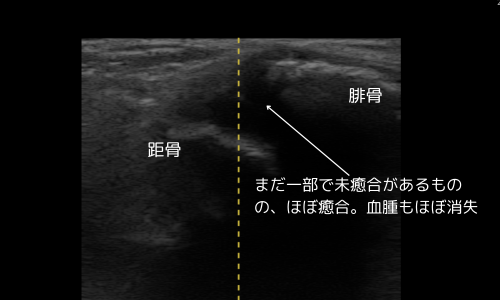

10月23日(受傷約1か月)

- 癒合ほぼ完了、医師および当院判断で施療終了

- ROM(可動域)も良好に回復